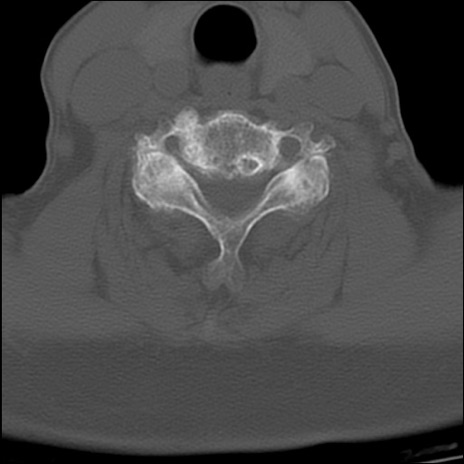

症例48 頚椎CT(横断像)

頚椎CT